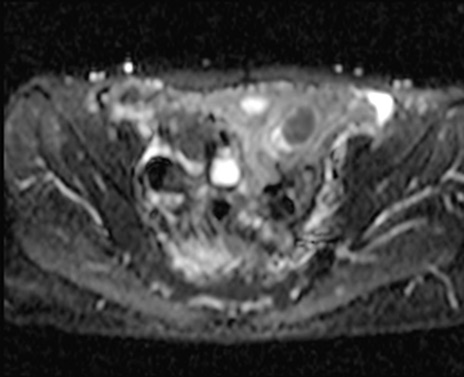

MRI(4日後)